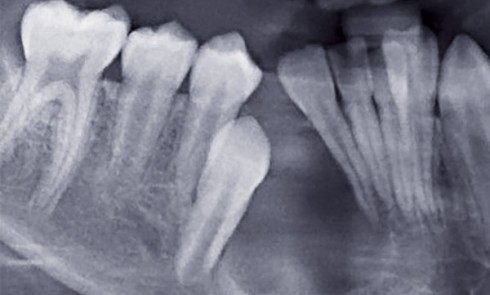

Article réservé à nos abonnés Démarche diagnostique clinique et radiologique face à une dent incluse

L’inclusion dentaire est définie comme une « dent retenue dans l’arcade maxillaire ou mandibulaire au-delà de la date d’éruption, entourée de...

Article réservé à nos abonnés L’inclusion dentaire : définitions, fréquence, causes

Devant tout retard d’éruption, il faut effectuer un bilan clinique et radiologique à la recherche d’une anomalie locale (kyste, odontome…)...